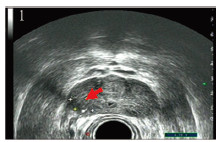

TRUS、CEUS、DCE-MRI三种影像学检查方法对前列腺癌的诊断价值差异无统计学意义(P=0.199)。以病理诊断证实为前列腺癌的患者分别在CEUS及DCE-MRI中漏报情况见表 2~3。前列腺癌病灶在TRUS和CEUS的声像图中的典型表现见图 1~2,在DCE-MRI中的典型表现见图 3~4。TRUS、CEUS及DCE-MRI诊断前列腺癌的ROC曲线见表 4、图 5。

| 图 1 经直肠超声图可见右侧外腺界线模糊局限性低回声区 Figure 1 TRUS image showed right outer gland with fuzzy boundary and limited low echo area |

| 图 2 超声造影图可见右侧外腺病灶区较周围前列腺实质明显强化 Figure 2 CEUS image showed right outer gland lesion area was significantly enhanced |